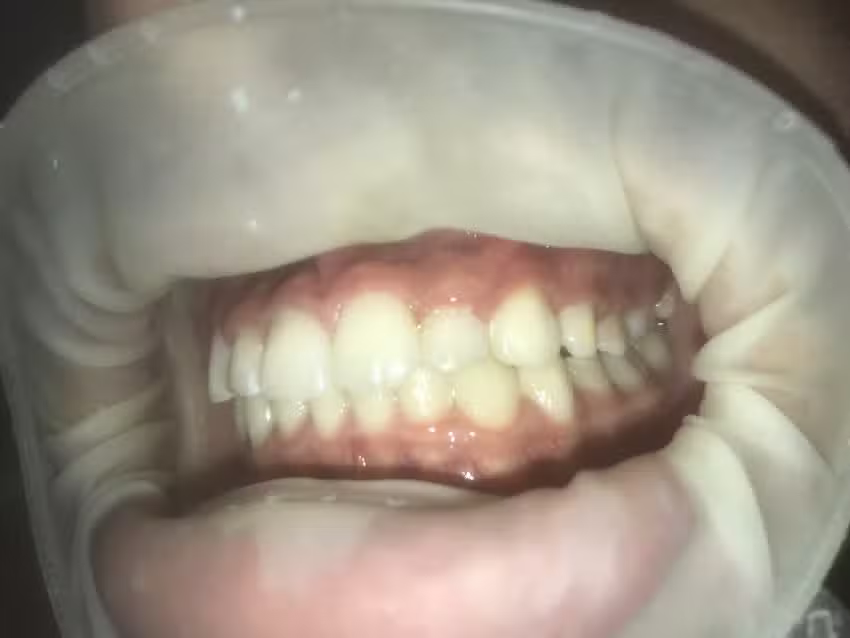

Entre los aspectos más positivos del lugar sobresale la especialización en ortodoncia moderna. Los pacientes mencionan que la doctora se mantiene actualizada en técnicas como los brackets estéticos y los alineadores dentales invisibles, una opción que gana terreno entre quienes priorizan la estética durante su tratamiento. También se valora la amplitud del consultorio y la limpieza del entorno, factores esenciales en un espacio de atención sanitaria. Las fotos compartidas en redes muestran un ambiente ordenado, con equipamiento de nueva generación y una atmósfera profesional.

En redes sociales, la presencia de la clínica es sobria pero cercana. La cuenta oficial de la Dra. Acosta en Instagram refleja un enfoque profesional que combina educación con promoción de resultados reales. Allí se comparten consejos de cuidado dental, tips sobre higiene oral y explicaciones claras sobre el uso de brackets autoligables o alineadores invisibles. Este tipo de contenido contribuye a construir confianza y refuerza la imagen de una especialista comprometida con la salud y la estética dental.

Además, varios pacientes jóvenes valoran la forma en que la doctora integra tecnología digital en la práctica. Se comenta el uso de escáneres intraorales y herramientas de planificación que permiten prever los resultados del tratamiento antes de colocarlo definitivamente. Ese enfoque moderno, basado en precisión y previsibilidad, marca una diferencia frente a técnicas tradicionales y contribuye a reforzar la reputación del consultorio como un espacio de odontología avanzada.